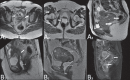

Magnetic resonance imaging is a method with high contrast resolution widely used in the assessment of pelvic gynecological diseases. However, the potential of such method to diagnose vaginal lesions is still underestimated, probably due to the scarce literature approaching the theme, the poor familiarity of radiologists with vaginal diseases, some of them relatively rare, and to the many peculiarities involved in the assessment of the vagina. Thus, the authors illustrate the role of magnetic resonance imaging in the evaluation of vaginal diseases and the main relevant findings to be considered in the clinical decision making process.